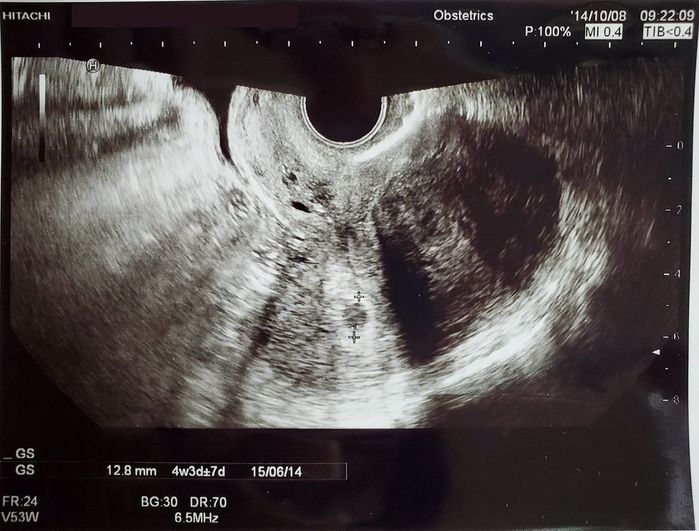

妊娠4週目のエコー写真 - 胎嚢が確認できました

検査薬で陽性反応があり婦人科を受診。高齢妊娠のため、不測の事態に備えて設備が整った総合病院を選びました。とても緊張しながら病院に向かい、モニターにうつる小さな丸い影を見て「本当に妊娠してる!」と思ったのです。1度流産を経験していたこともあり、不安も多くまだまだ実感がありませんでした。